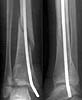

A female 14 y.o. sustained a spiral fracture of the distal tibia 1.5 years ago (Image 1). She was treated elsewhere by closed retrograde nailing with a thin nail (Image 2). The nail was removed after healing.

Image 1